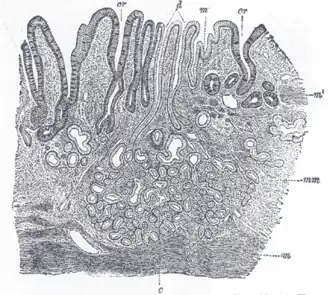

![]() Section of duodenum of cat. X 60. (Muscularis mucosae labeled at right, third from the top.) | |

The muscularis mucosae (or lamina muscularis mucosae) is a thin layer (lamina) of muscle of the gastrointestinal tract, located outside the lamina propria, and separating it from the submucosa. It is present in a continuous fashion from the esophagus to the upper rectum (the exact nomenclature of the rectum's muscle layers is still being debated). A discontinuous muscularis mucosae–like muscle layer is present in the urinary tract, from the renal pelvis to the bladder; as it is discontinuous, it should not be regarded as a true muscularis mucosae.

The muscularis mucosae is composed of several thin layers of smooth muscle fibers oriented in different ways which keep the mucosal surface and underlying glands in a constant state of gentle agitation to expel contents of glandular crypts and enhance contact between epithelium and the contents of the lumen.